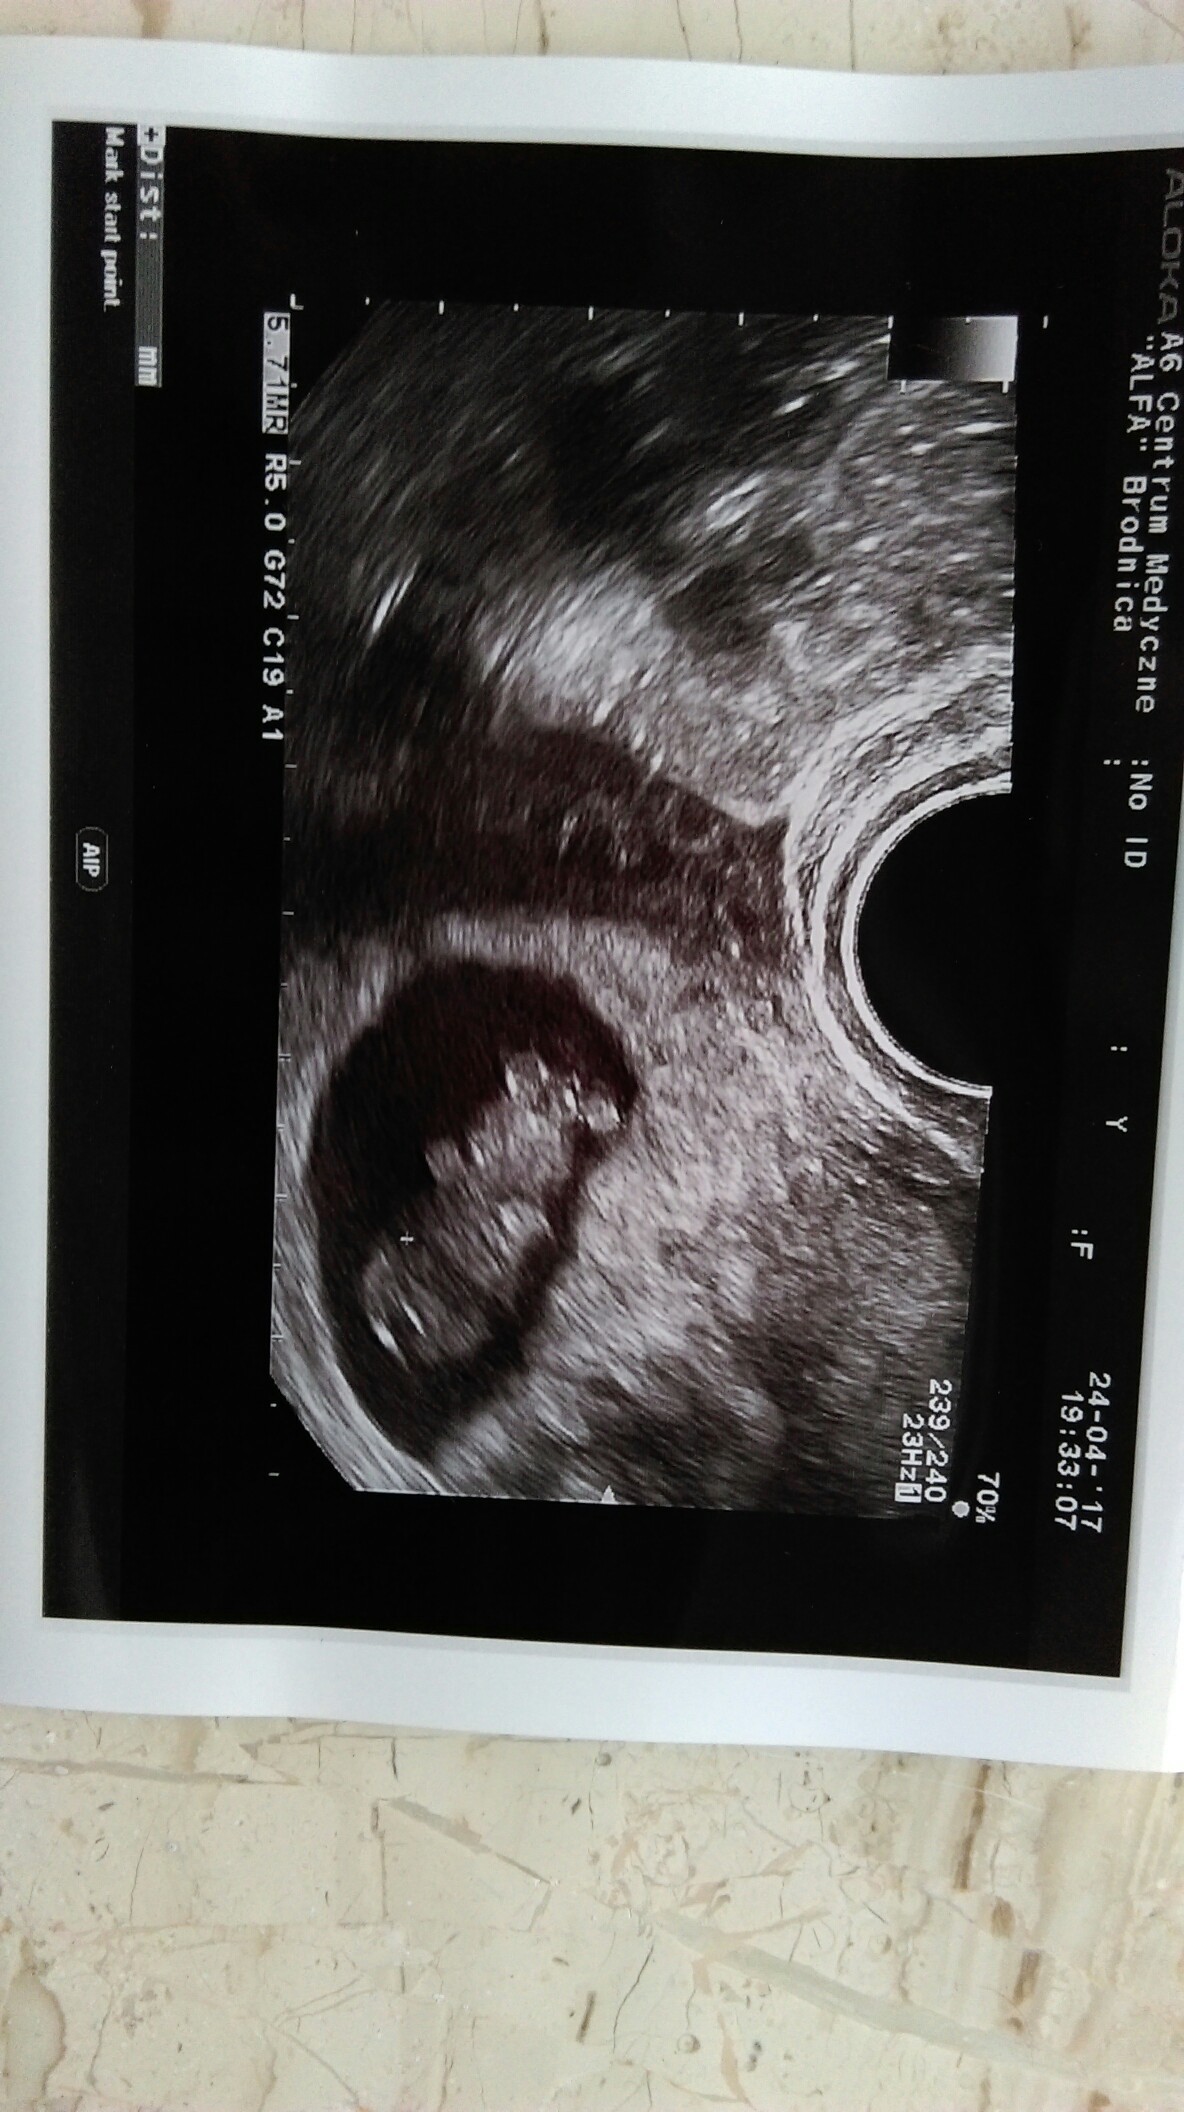

Już konkretna dzidzia [emoji7]Mój pajacyk9tydz, 23mm

o łaaa. już tak ładnie widać. Suuuper.Mój pajacyk9tydz, 23mm